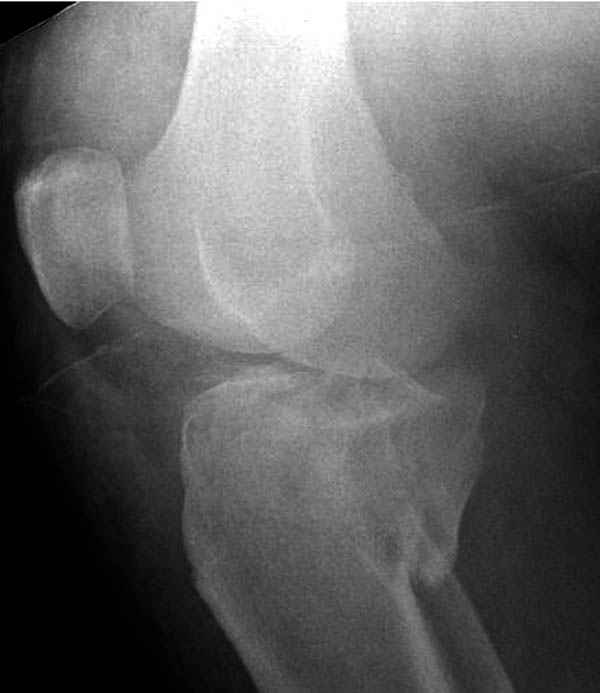

Трудно поверить, что разрекламированная Ортопедическая школа Восточной Украины позволяет такие странные снимки? На прямом снимке сохранен общий контур плато, но не известна судьба импрессии суставной поверхности. На полубоковой?, оставлен без репозиции задне-медиальный отдел, и навряд ли после такой фиксации можно удовлетвориться результатом.

Такая ситуация характерна для многих, когда принимается ошибочное решение, т.е пытаются фиксировать одним имплантом переломы двух мыщелков. Латеральная пластина приемлема только для тех случаев, когда сохраняется интактным медиальный диафизарный кортекс и отсутствует фрагментация на верхушке медиального перелома.

Здесь как раз тот случай, когда результат зависит не только от мастерства хирурга, но и от наличия современных методов исследования. Например, КТ которая поможет рассчитать направления шурупов и установку импланта. Кроме этого, поможет определиться с доступом.

На представленных предоперационных срезах КТ огромный задне-медиальный фрагмент расположен больше кзади, чем медиально. Для планирования, кроме поперечных срезов, надо ориентироваться на корональные срезы, которые укажут топографию верхушки медиального фрагмента.

Надеюсь, представленные снимки разных случаев помогут разобраться в тактике, и критика примется без личной обиды.